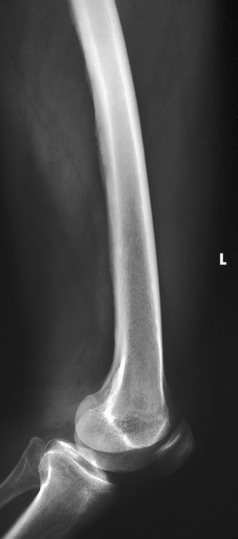

Structures shown: The resulting radiograph shows a lateral image of the distal end of the femur, patella, knee joint, proximal ends of the tibia and fibula, and adjacent soft tissue (Fig. 6-126).

Structures shown: The image shows a lateral projection of about three fourths of the femur and the adjacent joint. If needed, use two IRs to show the entire length of the adult femur (Figs. 6-169 and 6-170).